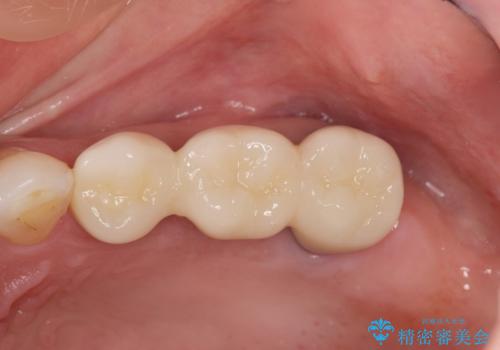

自然な仕上がりのブリッジ治療を達成することができ満足いただくことができました。

- 50.6万円(ジルコニアクラウン×3・仮歯×3・歯槽堤保存術)費用は治療当時の料金となります